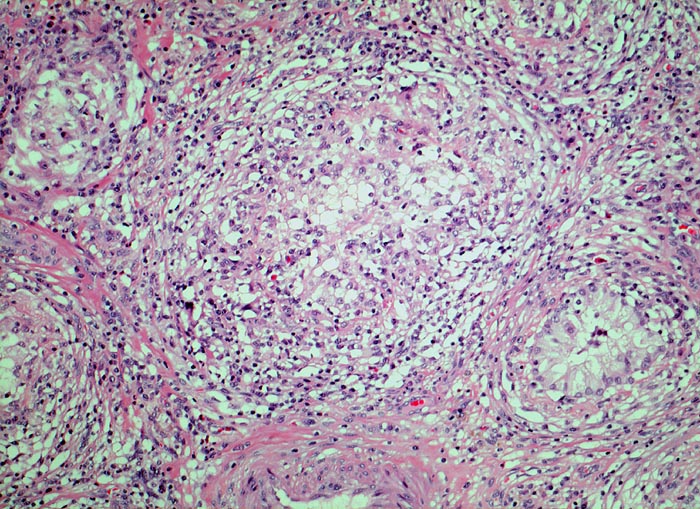

Idiopathische granulomatöse Orchitis

Die Hodentubuli sind atroph und kaum noch erkennbar im dichten gemischten Entzündungsinfiltrat.

Kein Erregernachweis.

Fieber und einseitige Hodenschwellung.

Im Gegensatz zur infektiösen Orchitis finden sich neben interstitiellen auch intratubuläre Entzündungsinfiltrate und die Entzündung ist meist nur einseitig. Meist finden sich nur angedeutete Granulome bestehend aus Histiozyten und Riesenzellen.

Histologie

100